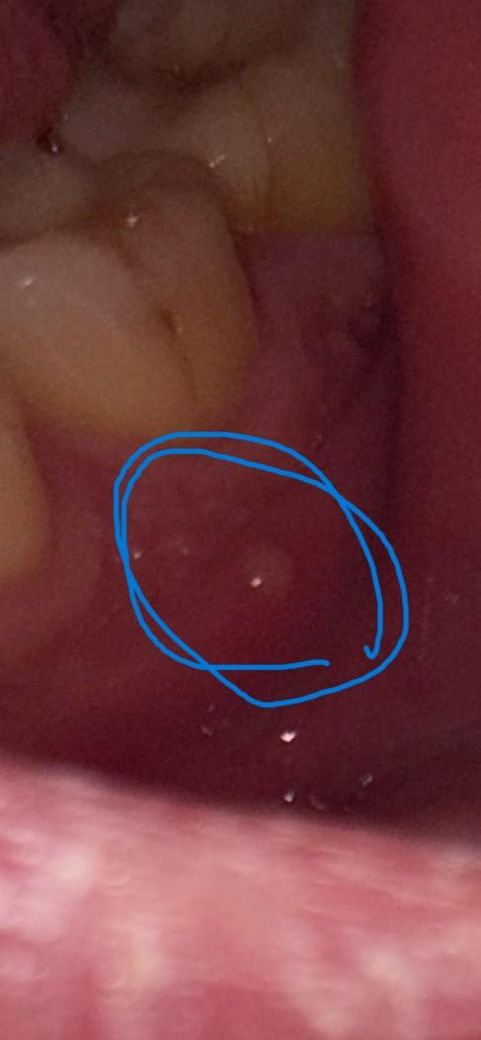

잇몸 뾰루지가 난 상황인데 이게 뭔가요..?

1. 오늘 갑자기 입술 안쪽 느낌이 이상해서 거울로 확인을 해보니 저렇게 뾰루지? 같은게 올라와 있네요..?

그냥 두면 없어지는 것인지 무조건 병원에 가야하는 건지 궁금해서 질문 올려봅니다 ㅠㅠ

최근에 반대쪽 사랑니 위아래를 빼고 1주일차인데, 혹시 연관이 있을까요? (뾰루지는 왼쪽 아래 발생, 사랑니는 왼쪽 위, 오른쪽 위와 아래 총 3개 발치한 상황)

• 1번 째 사진

단순 잇몸 염증일수도 잇고 치아 뿌리끝 염증일수도 있으니 일단 치과에 가셔서 검진을 받아보시는게 좋을것같습니다.

해당 부분은 치과가서 확인해보시는 게 좋겠습니다. 신경에 염증이 생겨서 그럴 수 있습니다.

치아 뿌리에 염증이 생기는 원인은 여러 가지가 있을 수 있습니다. 그 중에서 하나는 치수가 감염이 되어 치근단 질환을 유발했을 때 뾰루지와 같은 물집 형태로 고름주머니가 형성될 수 있습니다. 신경관에 감염이 충치로 인해서 생긴 것이라면 신경 치료와 보철 치료가 필요할 수 있습니다.

자세한 확인을 위해서 치과에서 진료를 받아보는 것을 권유드립니다.